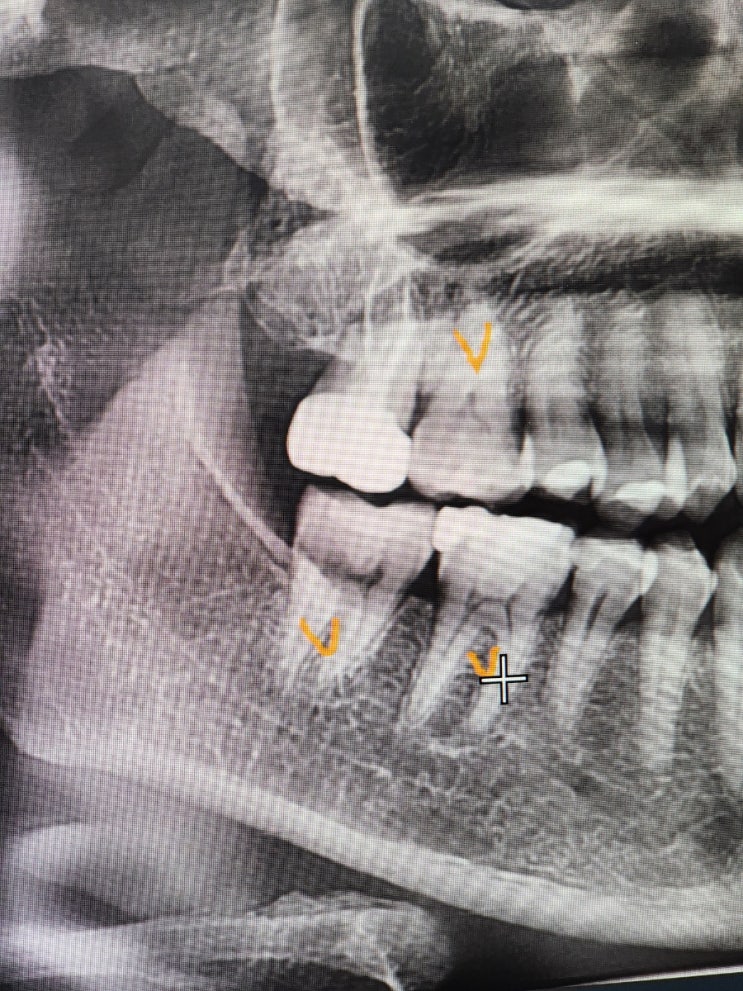

고강도 운동 어금니 크랙, 크라운 신경치료 1차 기록

24년 11월 19일 화요일 : 치과 두군데 견적 증상 오른쪽 어금니 위아래 통증이 있어서 질긴거랑 뜨거운거 ...